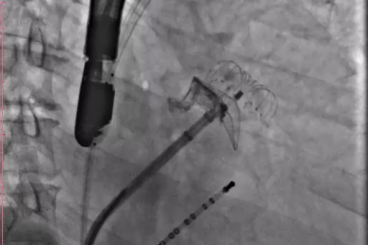

▲半发展固定伞,推送至锚定位锁死血栓

▲开释后,DSA与TEE观察均无残存分流

其中首场公开演示的左心耳血栓封堵病例拥有极高难度,患者术前TEE显示左心耳血栓形成伴机化,血栓位于心耳中段,近中端絮状物显著。封堵机遇只有一次,选型和操作稍有失误,城市增长手术风险。因而手术采取全麻,并装置了抗栓塞脑动脉;ぷ爸,以削减术中风险。通过TEE疏导下丈量左心耳大幼以及确认左心耳血栓地位,李岳春教授凭借自身丰硕经验最终决定使用LAmbre 2632型号,选取推送式植入法将左心耳血栓牢牢锁死于远端,并且封堵器一次成型,封堵成效极佳,实现后取出脑;ぷ爸,均未见血栓,顺利实现了此台高难度的手术,获得了学员们的一致认可。